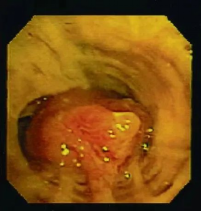

二、恶性中心气道狭窄

恶性中心气道狭窄是指气管、隆突、左右主支气管及中间段支气管因原发或转移的恶性肿瘤引起的气道狭窄。这类气道狭窄是气道支架置入的绝对适应症,气道支架置入后能够迅速解除梗阻,缓解呼吸困难,提高患者生存质量,为后续的肿瘤治疗赢得时间。

气道肿瘤致气道重度狭窄    气道支架置入后气道打开